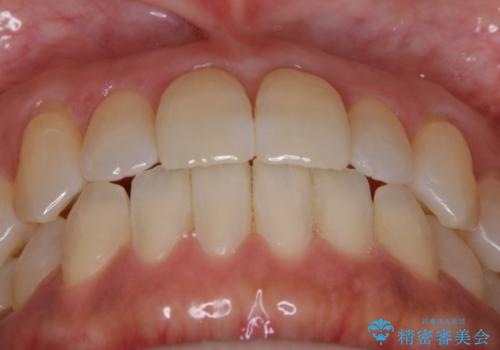

【非抜歯】短期間で実現する前歯の反対咬合治療

拡大とIPR

歯列の幅を拡大することにより作れるスペースは想像より大きく、実際に拡大だけでガタつきが治せるというケースもあります。

その他の歯のガタつきをとるためのスペース作りの方法の一つにディスキング(IPR)という方法があります。

歯と歯の間を一ケ所あたり最大0.5mmまでの範囲内で削ることで歯自体が少し小さくなり、それにより作られるスペースを数ヶ所分合わせることで合計で数mmの大きなスペースが作れるという方法です。